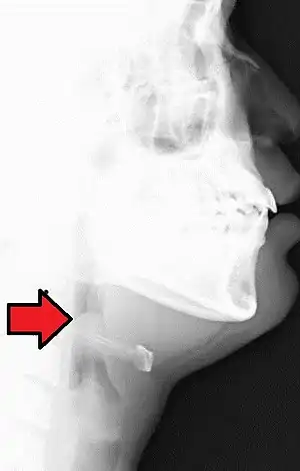

بیماری با گلودرد شروع شده و به سرعت شدت پیدا کرده و طی چند ساعت منجر به سختی بلع غذا (و ریزش بزاق) میشود. بیمار تب دار بودهاست و بیمار طی ۶ ساعت اول دچار اختلال در تنفس شده و صداهای خشن تنفسی (hoarseness of voice and stridor) پیدا میکند. در صورت عدم درمان بیماری میتواند کشنده باشد (اورژانس). از معاینه ته حلق بیمار بدون وجود امکانات پیشگیرانه بایستی اجتناب کرد. لارنگوسکوپی و گرفتن رادیوگرافی ساده گردن (دیدن علامت شست در گرافی) به تشخیص در مرحله اول کمک میکند.